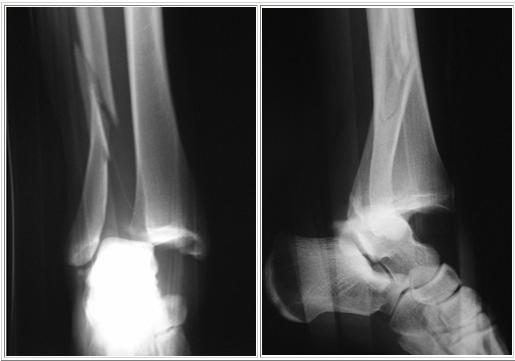

Patient consulte aux urgences pour douleurs importantes de cheville et impotence fonctionnelle après une chute. Des radios sont faites: quel diagnostic? Quel est le mécanisme lésionnel probable?

Fracture bimalléolaire de cheville sous-tuberculaire

mécanisme en aDduction forcée